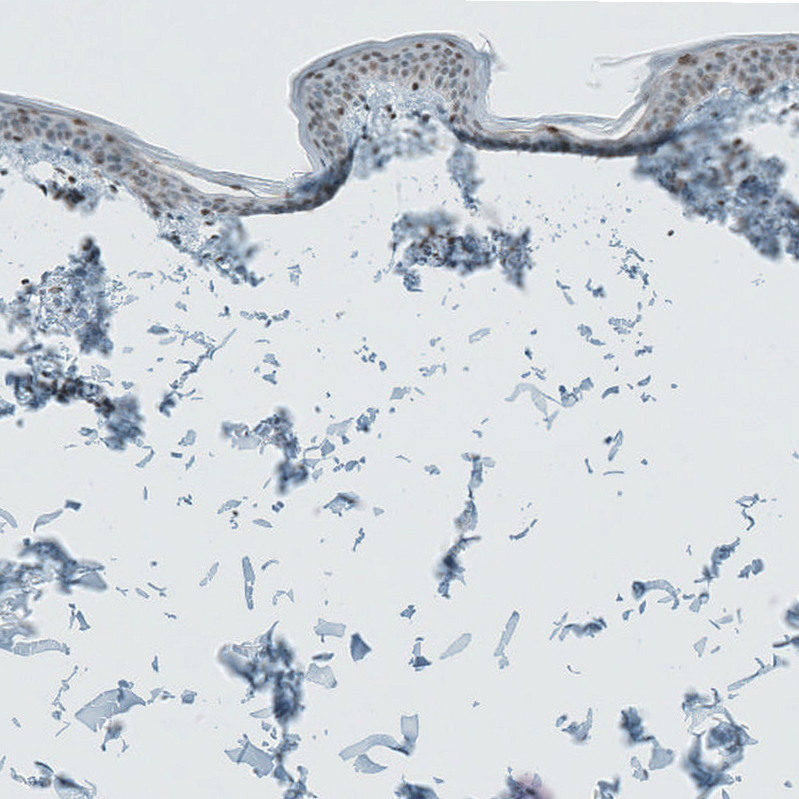

Immunohistochemical staining of human Skin shows moderate nuclear positivity in keratinocytes.